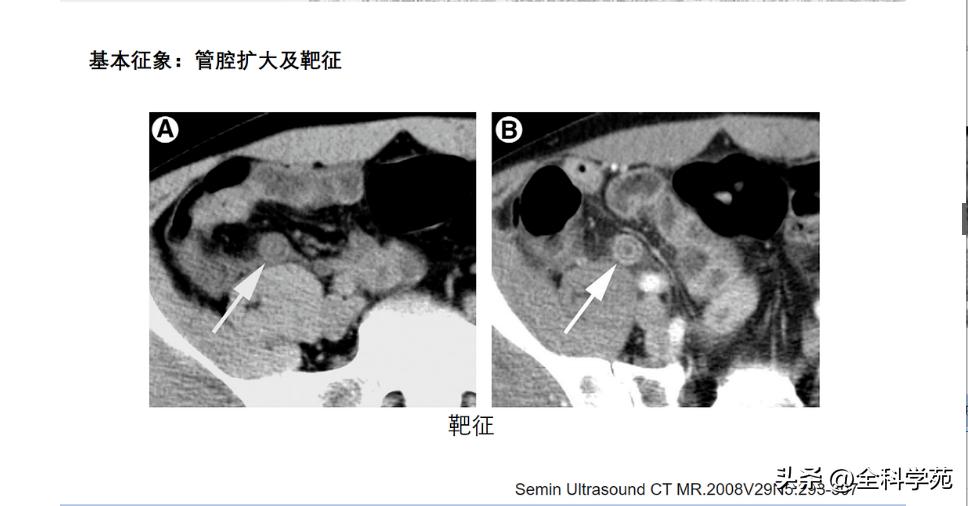

◆ 阑尾的内径增宽

> 10 mm

6-10 mm 伴阑尾壁增厚、壁明显强化,周围脂肪间隙模糊或分层(靶征或牛眼征,表明粘膜下水肿的液体含量vs 气体含量